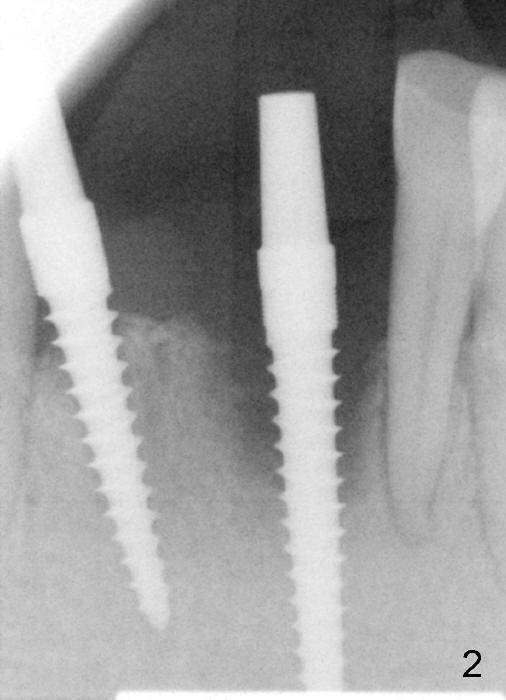

A 67-year-old man has a fixed partial denture (FPD) spanning from #24 to #26 (Fig.1). Originally the abutment #24 has endo perio disease. Finally the tooth #26 fractures. Both of the teeth are extracted and replaced by one piece implants (Fig.2). Placement of the immediate implant at the site of #24 is difficult due to the fact that the socket is deep and that surgical visibility is poor. An incision has to be made for the placement, followed by bone graft and collagen membrane. Tension is released prior to suturing. Two of immediate provisionals are fabricated over the one piece implants and a pontic is bonded to the retainers. Due to deep bite, the pontic is detached quick.